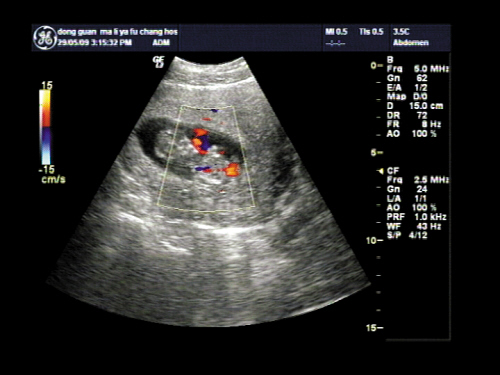

呼和浩特做彩超检查?【呼和浩特友谊医院】呼和浩特友谊医院妇科医师介绍说:彩超是目前的彩色超声仪器,它可有效的诊断胎儿是否存在先天性畸形,精准率高达99.99%。对于效果这么好的彩超,很多孕妈咪还不了解它的具体费用是多少。那么,呼和浩特做彩超检查的费用是多少呢?

四维彩超检查费用也不是很贵,一般来说只需几百块就可以了,是一般家庭都可以承受的,四维彩超检查的价格每个地方是不一样的,因为每个地方的收费标准存在差异,所以四维彩超的价格是不可以一概而论的,但是建议广大孕妈妈们还是到正规医院做四维彩超,因为正规的医院收费都是标准的。了解彩超检查的更多信息,可在线咨询医师